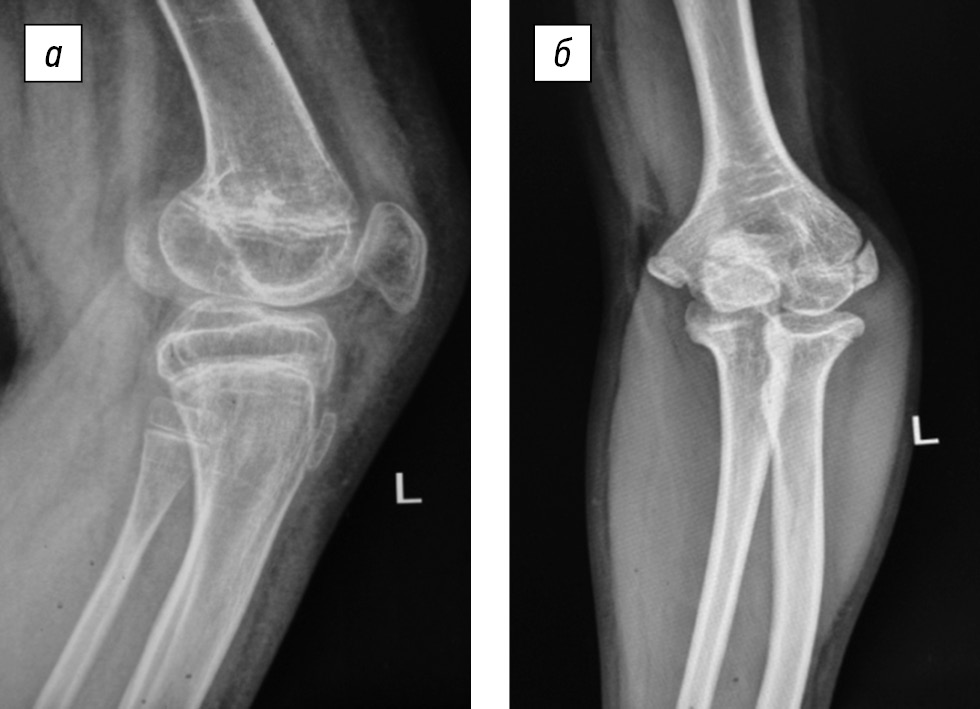

Concurrently, other anatomical and functional disorders of the affected limb segments appeared in the growth process, namely, left femur shortening and left femur and tibia antecurvation deformity, which imitates knee joint flexion contracture, as well as left elbow joint varus deformity (2020) (Fig. 3).

Fig. 3. Left knee (a) and elbow (b) joint deformities at the treatment stage